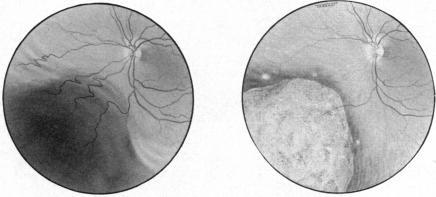

Radiotherapy for malignant melanoma of the choroid.

Br J Ophthalmol. 1966 Mar;50(3):147-55. doi: 10.1136/bjo.50.3.147.